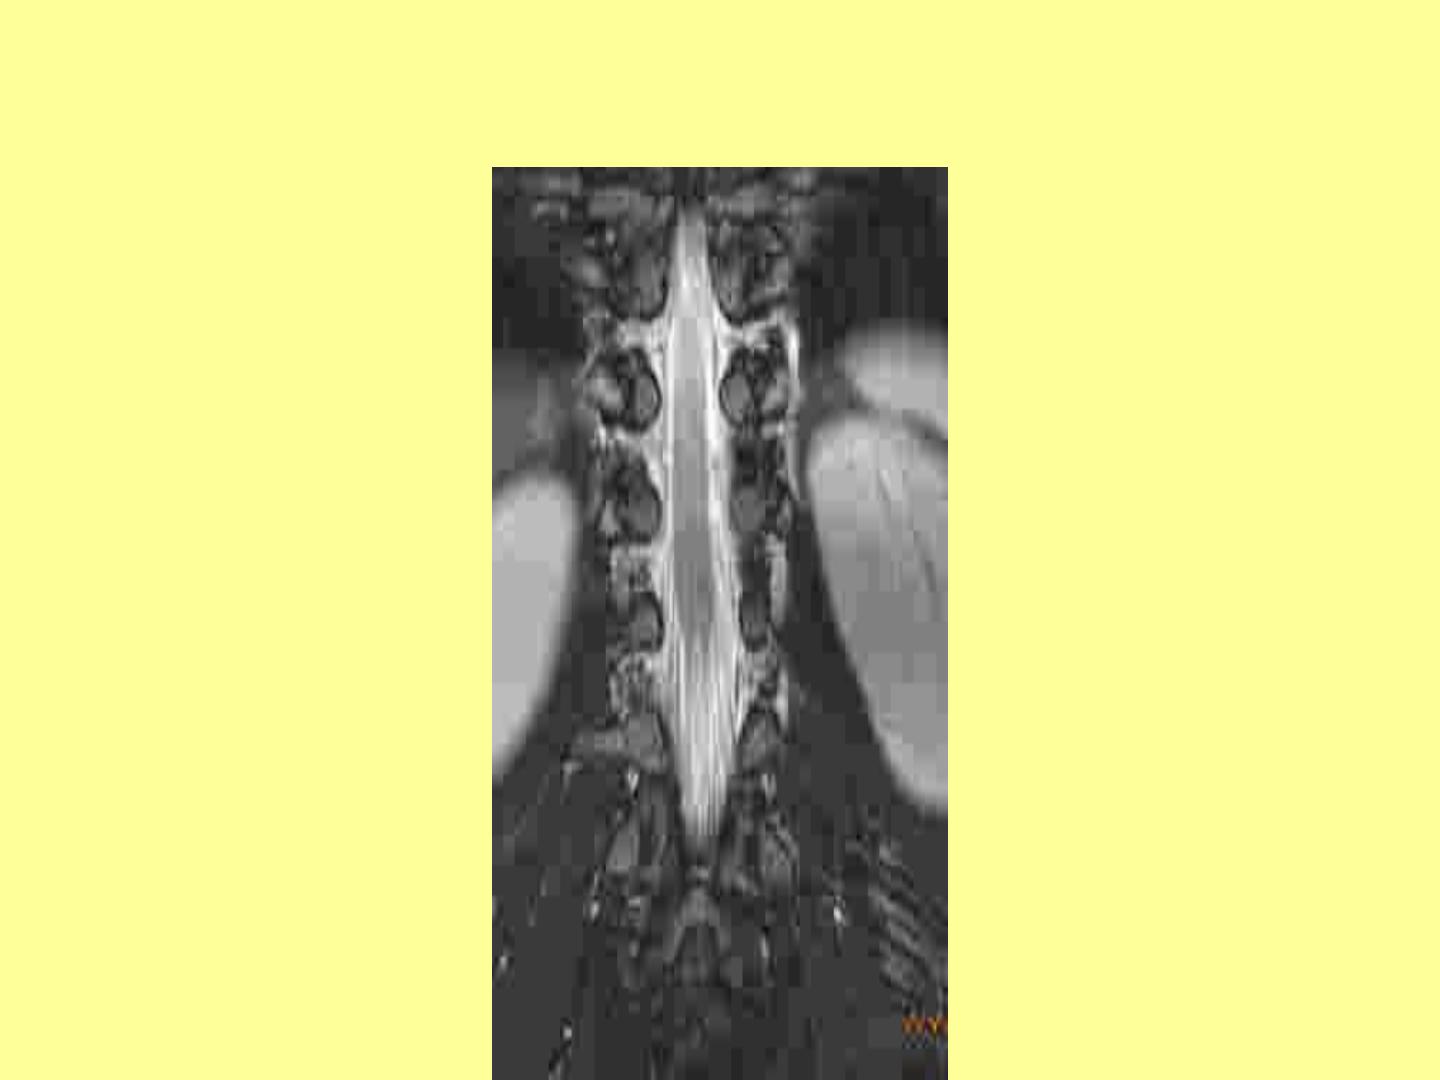

QUEUE DE CHEVAL